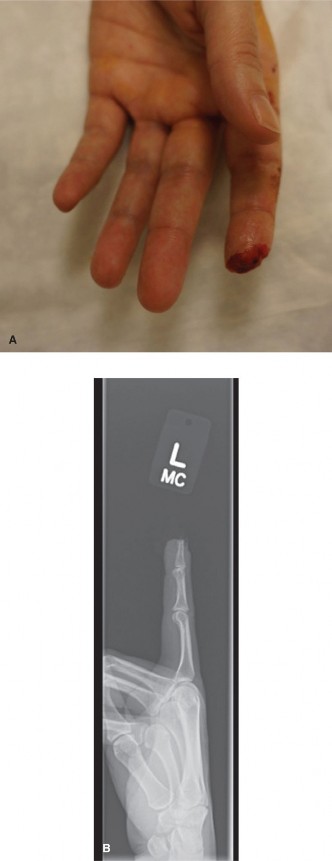

Epidermoid inclusion cysts develop from the traumatic implantation of epithelial cells into the deep subcutaneous tissues or bone. The clinical history almost universally involves a penetrating wound (e.g., a needle prick, thorn, or crush injury) to the palm or fingertip several months or even years prior to presentation.

Clinically, the patient develops a hard, rubbery, non-tender subcutaneous mass. The distal phalanx is the most common osseous site, where the expanding cyst can cause pressure erosion of the bone.

Clinical appearance of an epidermoid inclusion cyst on the index finger following a remote puncture wound.